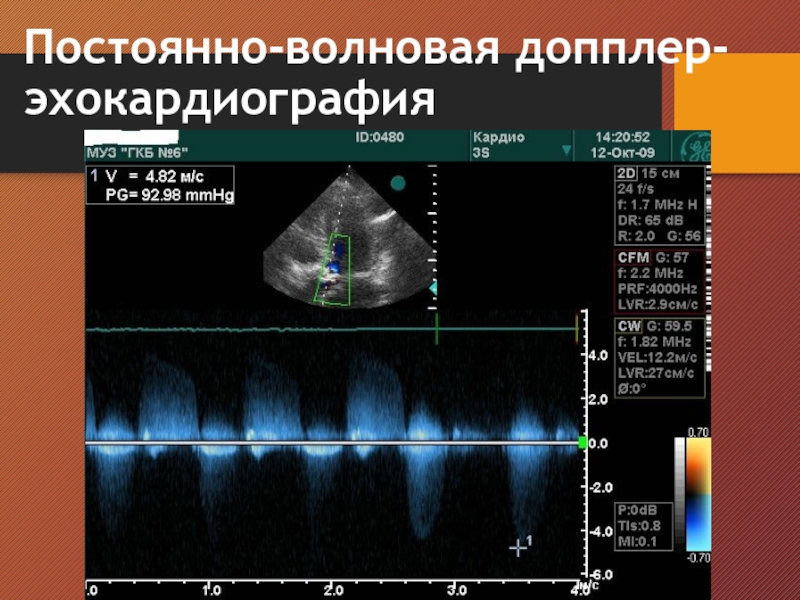

Слайд 16Постоянно-волновая допплер-эхокардиография

Постоянно-волновая допплер-эхокардиография